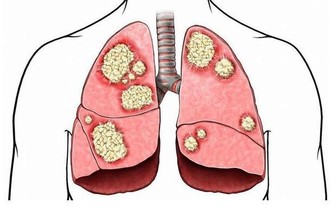

鼻毛能夠有效過濾外界的雜質,防止灰塵進入到我們的身體當中,損傷我們的肺部健康,這一點是保護肺臟的作用。我們的身體離不開呼吸,24小時裡鼻腔都在進行工作,